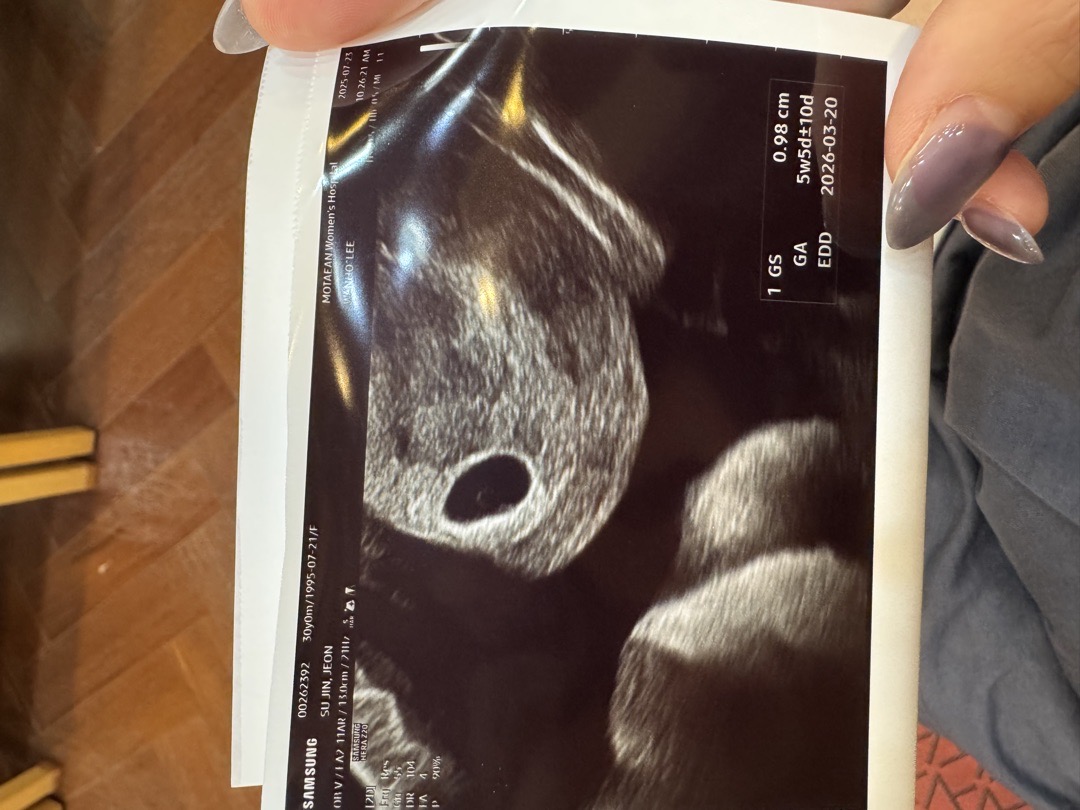

난황 보이실까요??

5주5일로 찍히는데 초음파 보시면 0.98mm인데 난황 아직 안보여서요!!

보여요! 동그란거 난황 맞는거 같아요!

저랑 예정일 같으시네요 초음파가 단면이다보니 난황부분이 좀 짤린거같아요